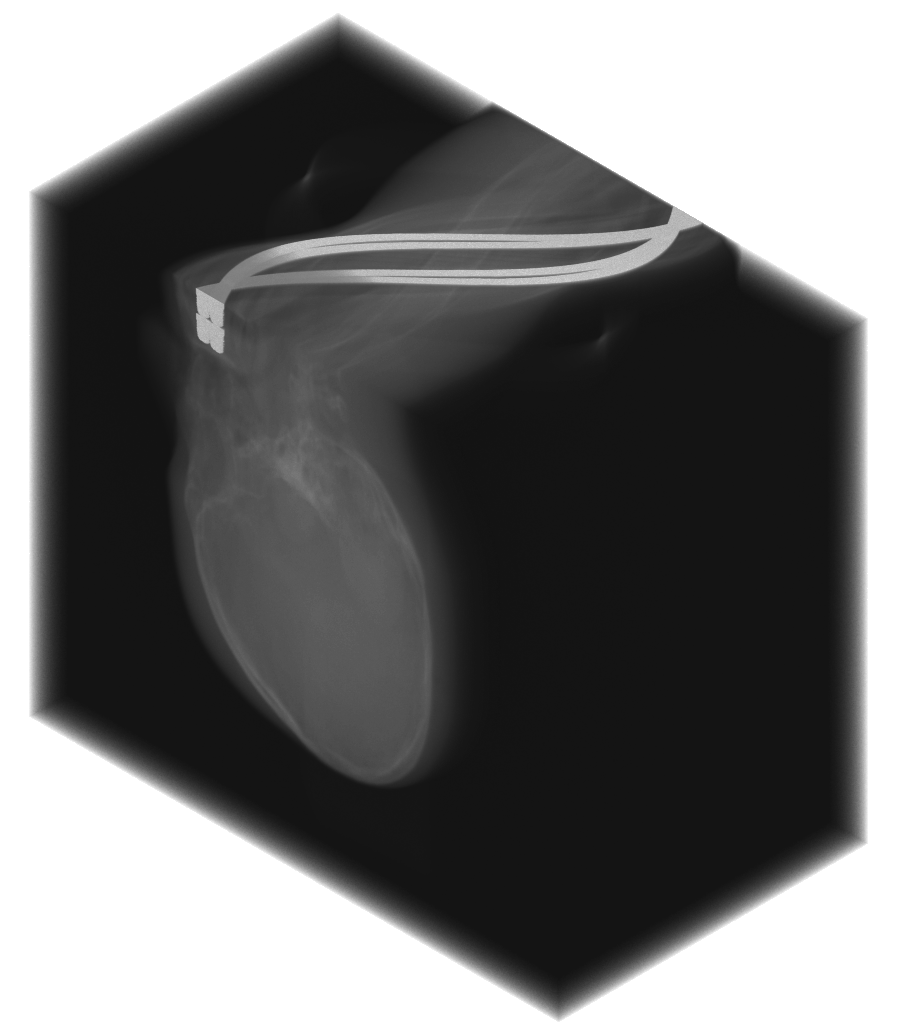

The experimental datasets include: (III) a tooth embedded in gelatin with an amalgam filling, (IV) a high-gold alloy fixed dental prosthesis, and (V) an anthropomorphic phantom containing a metal screw partially outside the reconstruction field of view.

We computed the uncorrected FDK reconstruction, the image-domain hard-thresholding–based MAR reconstruction, and the proposed projection-domain complex wavelet MAR reconstruction for datasets (I–V). Fig. 4 shows selected slices from the reconstruction volumes for each dataset, displayed using identical windowing. The quantitative results of the metal segmentation are reported in Table 1 for datasets (I) and (II).

Dataset (V) presents a particularly challenging MAR scenario, in which the metal object is partially outside the reconstruction field of view (FOV). As a result, streaking artifacts are present even when the metal itself does not appear within the reconstructed volume. The large screw produces severe artifacts in the uncorrected FDK reconstruction. The image-domain HT-MAR approach is unable to reduce artifacts caused by metals outside the reconstruction FOV and additionally struggles with accurate boundary segmentation, especially in the coronal direction, where the screw geometry is particularly challenging. In contrast, the CW-MAR method is not affected by metals outside the reconstruction FOV, since segmentation is performed in the 3D sinogram domain, where the corresponding metal trace is present. Consequently, artifact reduction is effective. However, as in previous cases, projection inpainting introduces some blurring, which in this dataset leads to a loss of fine anatomical detail.